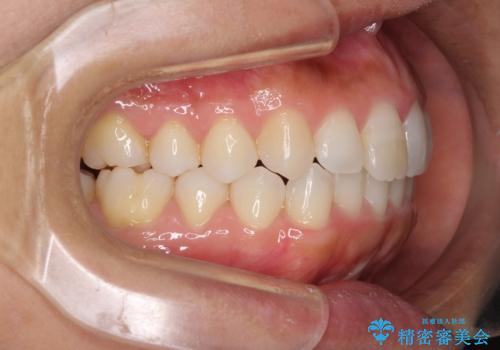

前歯の叢生を治したい インビザラインによる矯正治療

- 上下の前歯のデコボコと奥歯の反対咬合を気にして来院された患者様です。

インビザラインを用い、上下顎ともにIPR(歯と歯の間を削る)により叢生を改善することとしました。

奥歯の反対咬合は、骨格に由来するものであるため、改善できるところまで改善していくこととしました。

治療を長期化させたくないとのご要望があったので、左下の90度捻転した歯は、捻転した状態のゴールとしました。

反対咬合を改善したことで、歯ぎしりしたときの引っかかる感じがなくなり、奥歯への負担を大きく軽減することができました。